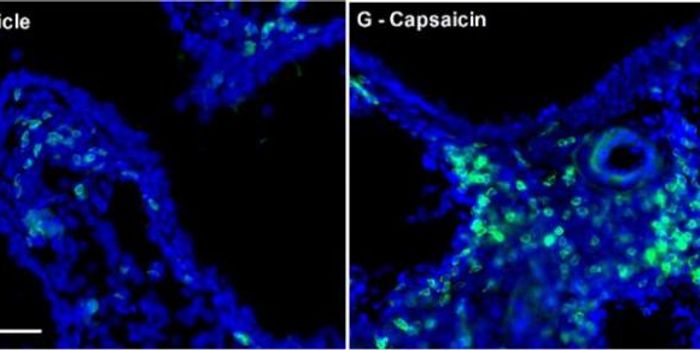

JUN 09, 2016Cannabis SciencesAs marijuana proves itself effective in treating a multitude of diseases, researchers are looking for problems associate ...

JUN 26, 2015NeuroscienceWhile asthma medications that suppress inflammatory signaling by immune cells or dilate airways are effective, they can ...